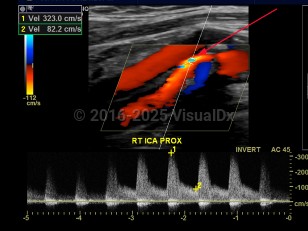

Carotid artery stenosis

Narrowing of the carotid artery lumen, usually due to atherosclerotic plaque formation. It is generally asymptomatic, although the risk of ischemic cerebrovascular accidents increases substantially with severe narrowing or obstruction of the arterial lumen.